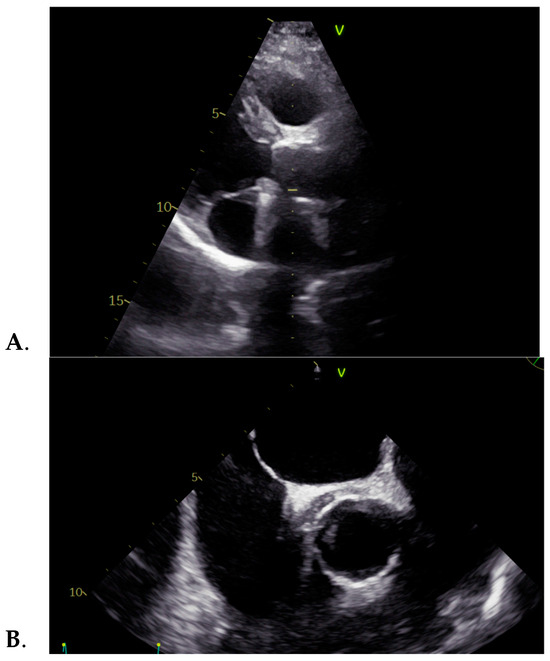

| -prolonged febrile syndrome -vertigo -pale skin -closing click in the aortic area | Mother died at 36 y (spontaneous carotid artery dissection) | Bentall procedure (for acute DeBakey type I aortic dissection) | -elevated ESR -elevated C-reactive protein -positive procalcitonin -negative blood cultures -elevated phase I and phase II IgG and IgM | -mechanical prosthesis in aortic position -12 mm echo-dense mass surrounding the ascending aorta | 2 years | Medical: -antibiotics: Doxycycline (100 mg/bid) and Hydroxychloroquine (200 mg/tid) -Acenocumeral 4 mg -Furosemide/Spironolactone 20/50 mg/day Surgical: removal of the periaortic hematoma |